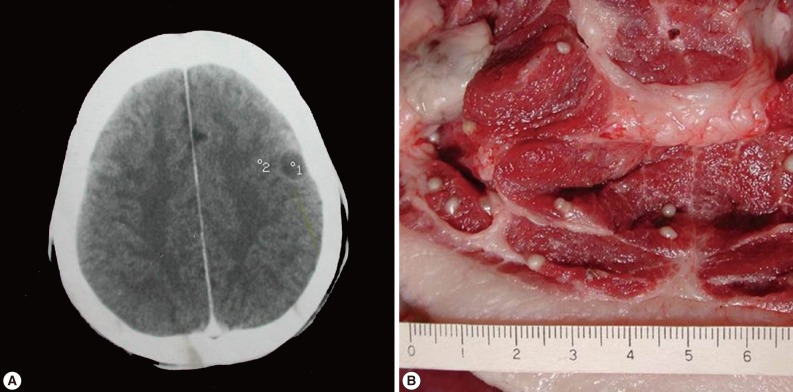

A male patient with neurocysticercosis was identified in Montai Village, Xay District, Oudomxay Province, Lao PDR while the author's group was visiting the place for a helminthological survey in February 2004. He visited our survey team and gave a history of diagnosis by CT scan in Thailand after an onset of epileptic seizure in 1993 (Fig. 2A). After treatment with albendazole (15 mg/kg, 3 times per day for 7 days, with prednisolone), he was followed up by CT scan 3 years later in Lao PDR and minimized calcified lesions were found. Three of his family members and relatives had the same or similar symptoms, such as headache. One of their favorite foods was chopped pork wrapped with banana leaf (Sommou). Serological diagnosis of cysticercosis was conducted on his family members (n=8) using ELISA. The serum antibody levels in patients with Taenia tapeworm infections were quantified by micro-ELISA. T. solium metacestode antibodies were detected in sera collected from patients, with relative antibody levels in mean absorbance and SD of 0.20±0.04 or higher. Serum samples from 5 people (0.08±0.1) and 3 people (0.25±0.03) displayed significant levels of reactivity with T. solium metacestode antigen. All of them were subjected to coprological examinations by the Kato-Katz method for Taenia eggs but turned out to be negative in all. Further CT scan study was not implemented and subcutaneous nodules were all negative.

A pig was found by our team infected with T. solium metacestodes showing rostellar hooklets (more than 2,000 cysticerci in the whole body) upon slaughter in February 2004, in the same locality of the patient (Fig. 2B). According to the data from the government veterinarian of the Oudomxay Office of Agriculture, Forestry, Livestock, and Fisheries in Xay District, the prevalence of cysticerci-infected animals between February 2003 to October 2004 was 0.6% (46/7,826) in pigs and 3.1% (44/1,437) in cattle (Table 1). The most prevalent areas for cysticerci infection in pigs were Beng (Thameun, Namet, Napa), Namo (Nathong, Nasavang, Ban Khouang), and La (Parkla Lack) villages.

Fig. 2

(A) Vesicular cysticerci on contrasted CT scan. '°1' shows a small and rounded low-density area (1.5 cm diameter) in a patient with parenchymal neurocysticercosis. '°2' demonstrates a minimized calcifying lesion. (B) T. solium metacestodes in the flesh of a pig obtained from a slaughterhouse in Oudomxay, Lao PDR. The scale at the bottom of the picture represents a centimeter ruler with millimeter subdivisions.